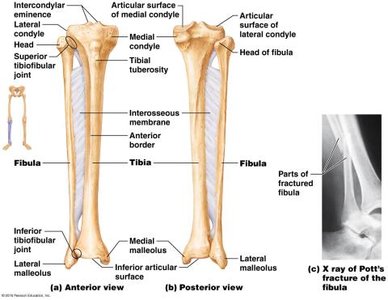

Tibia: Medial leg bone, weight-bearing; features include condyles, tuberosity, medial malleolus.

Fibula: Lateral leg bone, not weight-bearing; features include lateral malleolus.